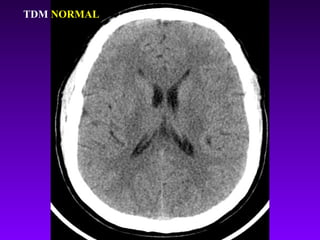

TDM cérébrale

TDM NORMAL

En urgence reconnaîtla lésion hémorragique sous forme d’une zone spontanément hyperdense. La lésion ischémique est sans traduction (en phase initiale) ou se manifeste par une zone hypodense (après 24 h). TDM cérébrale